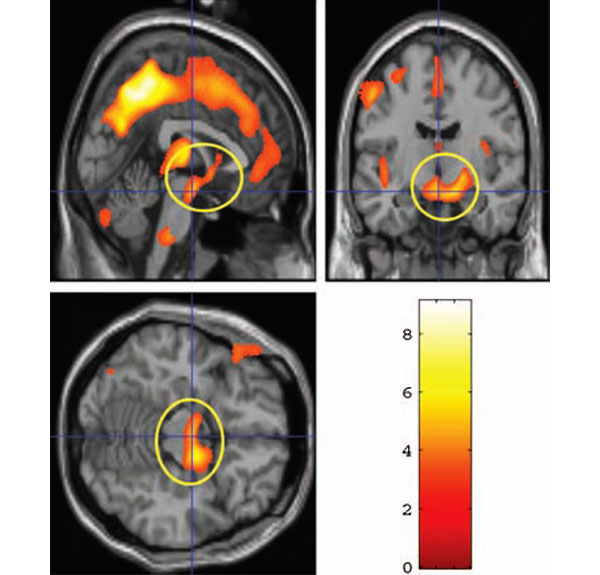

Участки коры, в которых у матерей увеличивается объем серого вещества

Желтым кружком обведены участки среднего мозга, в которых рост объема серого вещества положительно коррелирует со степенью восторженности, выраженной матерью по отношению к своему ребенку через 2-4 недели после родов. Разными цветами показана степень статистической достоверности того, что объем серого вещества в данной области действительно увеличился

Оказалось, что количество восторженных эпитетов, которыми мать наградила своего малыша во время тестирования через 2-4 недели после родов, является хорошим предиктором роста серого вещества в гипоталамусе, миндалине и substantia nigra в последующие 2-3 месяца: кто выбрал больше эпитетов, у того и прибавилось больше серого вещества в этих отделах. Степень восторженности по отношению к материнству, однако, не коррелирует с ростом серого вещества.